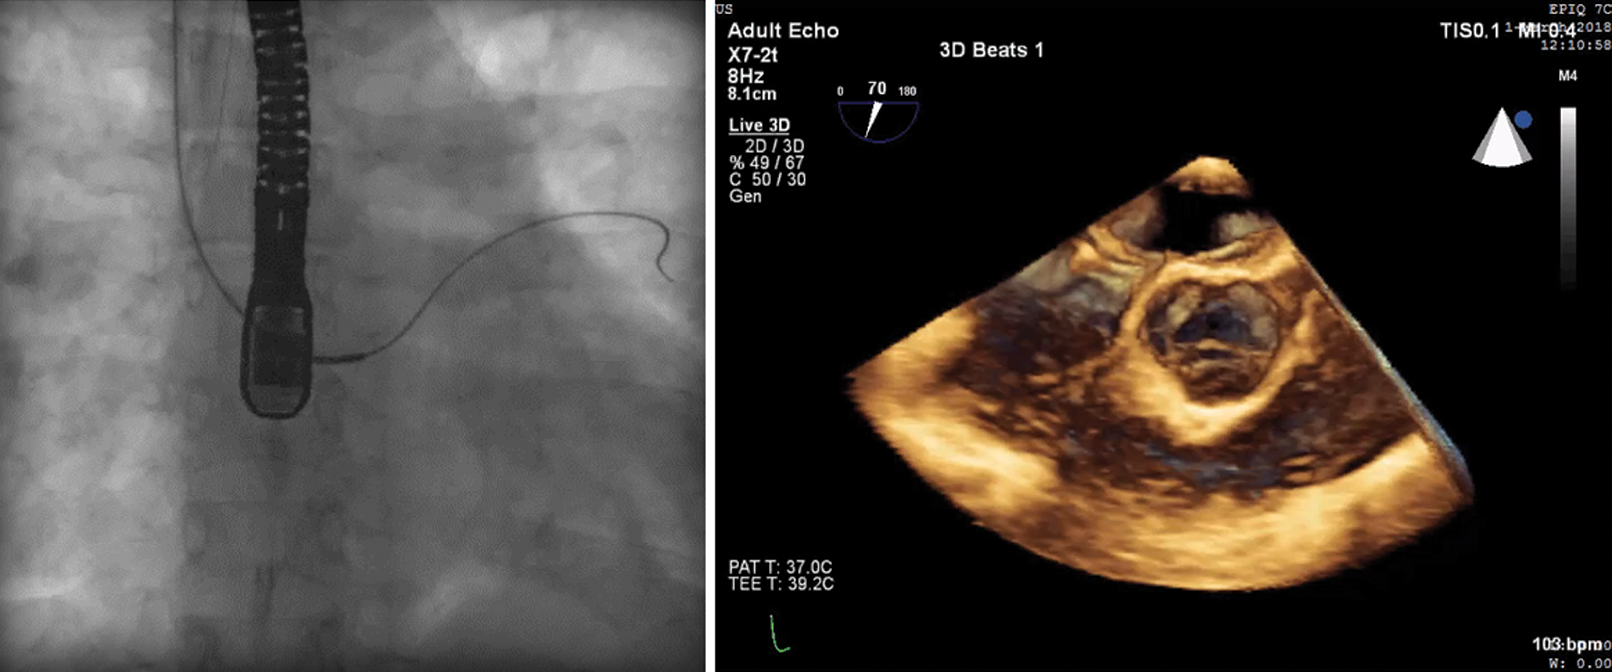

The Heart Team decided to proceed to ASD closure via the right internal jugular vein (IJV) approach. The procedure was performed under general anesthesia and continuous TEE monitoring. After insertion of a femoral artery line for hemodynamic monitoring, a 100-U/kg bolus of heparin was administered. A 6F right IJV sheath access was introduced and a 6 Fr Cobra catheter (Cook Medical) was easily negotiated through the defect, although stable sheath position in the LA could not be maintained. Following, a 9Fr steerable sheath (Fustar Steerable Introducer sheath, Lifetech Scientific, Shenzen) was engaged to advance a 6Fr multipurpose catheter into the LA over a 0.035” 145 cm J-tip guidewire (Bard Medical). However, since a 0.035” stainless steel wire was not supporting sheath passage into the LA, a 0.035” 260 cm Amplatz super-stiff guidewire (Cook Corporation) was exchanged and introduced via the multipurpose catheter. The wire was not maintaining a stable position in any of the pulmonary veins (Fig. 2).

Figure 2: Fluoroscopy (left panel) and transesophageal echocardiography (right panel) images showing the wire in the left atrium through the atrial septal defect, unable to maintain a stable position in the pulmonary veins